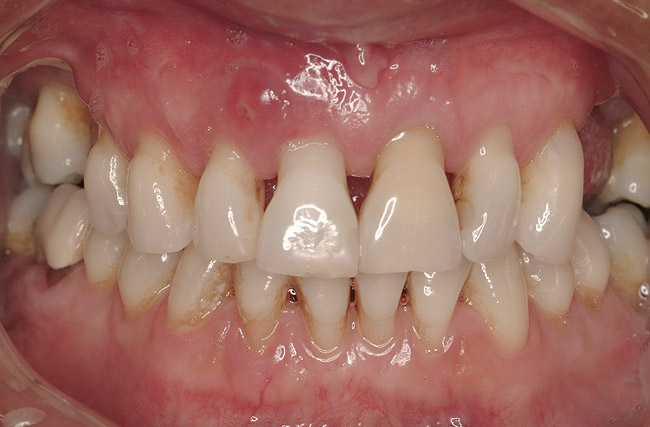

Figure 3  Pre-extraction situation. Tooth Nos. 24 and 25 were planned for extraction, and simultaneous ridge augmentation was planned. Implant placement in these two positions at the conclusion of active tooth movement was also planned.

Figure 3

Figure 14  Severe periodontitis and periodontal abscess on the facial aspect of tooth Nos. 7 and 8. All maxillary teeth were hypermobile and the patient was symptomatic in the anterior sextant.

Figure 14